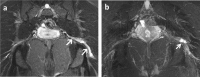

Acetabular paralabral cysts are common. They vary in their clinical presentation and may be asymptomatic or cause pain and restriction at the hip joint. In rare instances they may cause symptoms by compressing local neurovascular structures. We report a case of symptomatic compression of the sciatic nerve by a posteriorly displaced acetabular paralabral cyst.